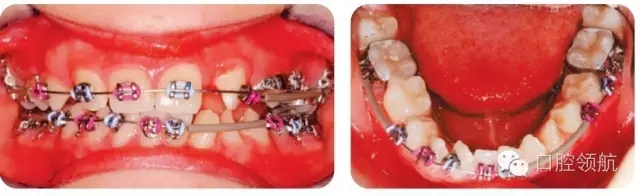

圖2.24中為何下頜有的牙齒未粘結(jié)托槽?

LL2和LL3幾乎扭轉(zhuǎn)90°,沒有足夠間隙改扭轉(zhuǎn)排齊。很難在扭轉(zhuǎn)牙的正確位置粘結(jié)托槽,所以在治療開始階段暫不納入,并用塑料套管支持弓絲,避免刺激軟組織。治療中推出間隙再排齊扭轉(zhuǎn)牙。

圖2.24